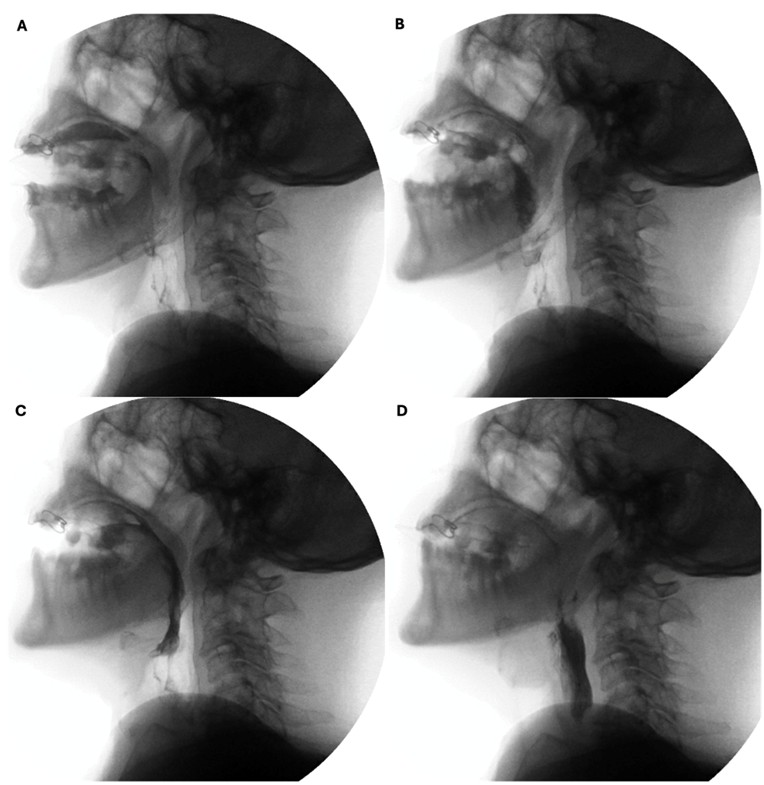

The preparatory phase of deglutition applies exclusively to the deglutition of solid food and boluses are prepared through a three-stage process that occurs simultaneously17: phase I transport - the tongue performs rotational movements to displace food posteriorly and laterally onto the occlusal surface of postcanine teeth; food processing - mastication and mixture of food with saliva alters the consistency of the boluses and prime it for swallowing; and phase II transport - processed food is pushed to the oropharynx, where it aggregates before being swallowed. By combining clinical and radiological evaluations, defects such as prolonged food processing time or reduced tongue movements can be identified. (Fig. 3)

Figure 3: Preparatory phase of a solid bolus shows mastication (A) followed by phase II transport to the oropharynx (B and C) before swallowing (D)